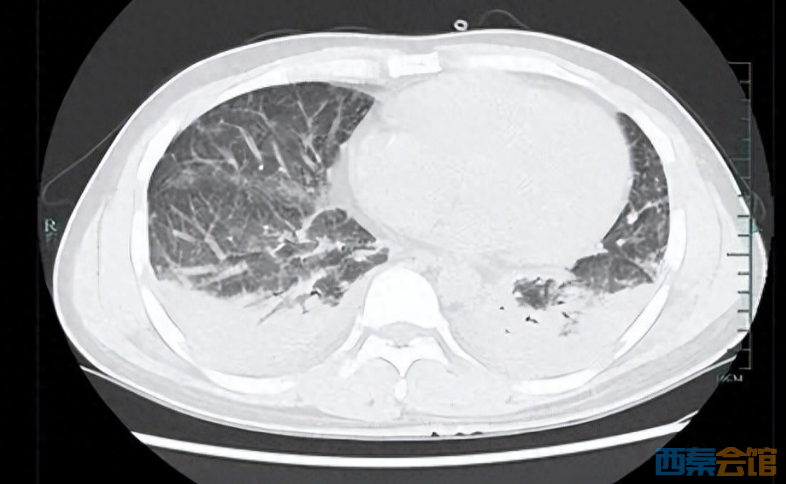

壮哥经检查:胸部CT双肺弥漫性病灶,血氧饱和度指标不到70%。“重症肺炎,I型呼吸衰竭。再拖下去有生命危险!”他随即被安排住院治疗,并做了基因检测,揪出了真凶——马尔尼菲篮状菌。

ScreenShot_2026-01-05_143317_995.png

壮哥的肺部情况

经过抗真菌等一系列治疗后,壮哥的呼吸衰竭症状明显改善,胸部CT复查也显示病灶明显吸收好转。如今,他已经临床治愈,带药出院回家进行巩固治疗。